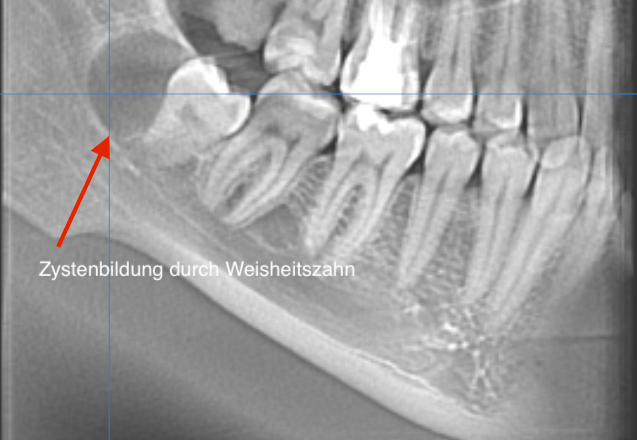

Sie können notwendig werden bei tief beschädigten, kariösen Zähnen oder bei nicht durchgebrochenen, retinierten Zähnen, d.h. solchen, die noch unter dem Zahnfleisch im Knochen liegen. Meistens handelt es sich bei letzteren um Weisheitszähne, jedoch auch Eckzähne oder kleine Backenzähne können „retiniert“ bleiben. Ab dem 30. Lebensjahr kann jeder nicht durchgebrochene Zahn ein Entzündungsherd im Körper sein. Oft verursachen Weisheitszähne jedoch schon früher Beschwerden und müssen daher entfernt werden.

Verlagerte Weisheitszähne und entzündetes Kieferknochengewebe können auf den dreidimensionalen DVT-Aufnahmen genau untersucht werden.

Durch den Einsatz der Volumentopographie lässt sich die Anzahl und Ausrichtung der Wurzelkanäle sowie die Position und Ausdehnung von Tumoren und Zysten besser darstellen.